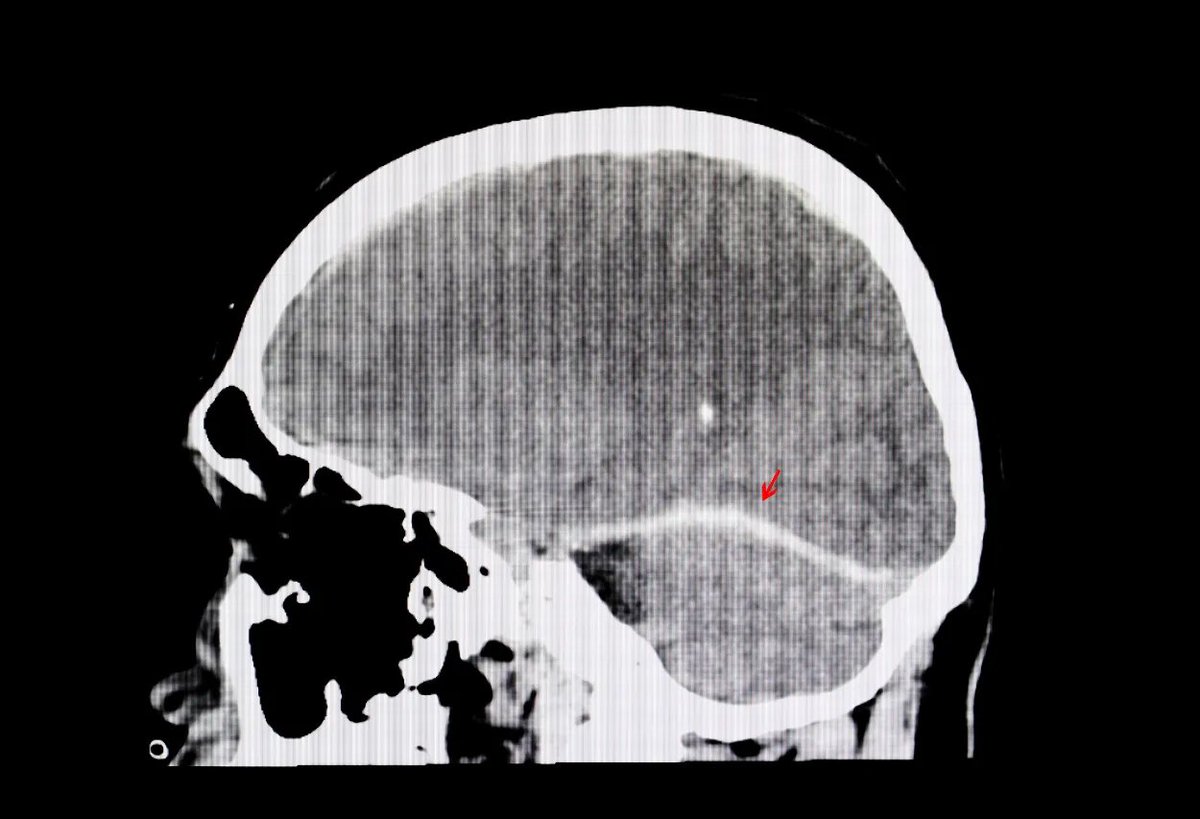

@MidwesternDoc Patients with severe head trauma and dangerously high brain pressure saw their pressure drop within minutes of IV DMSO.

CT scans confirmed swelling reduced.

Many went from near death to minimal or no impairment. Image